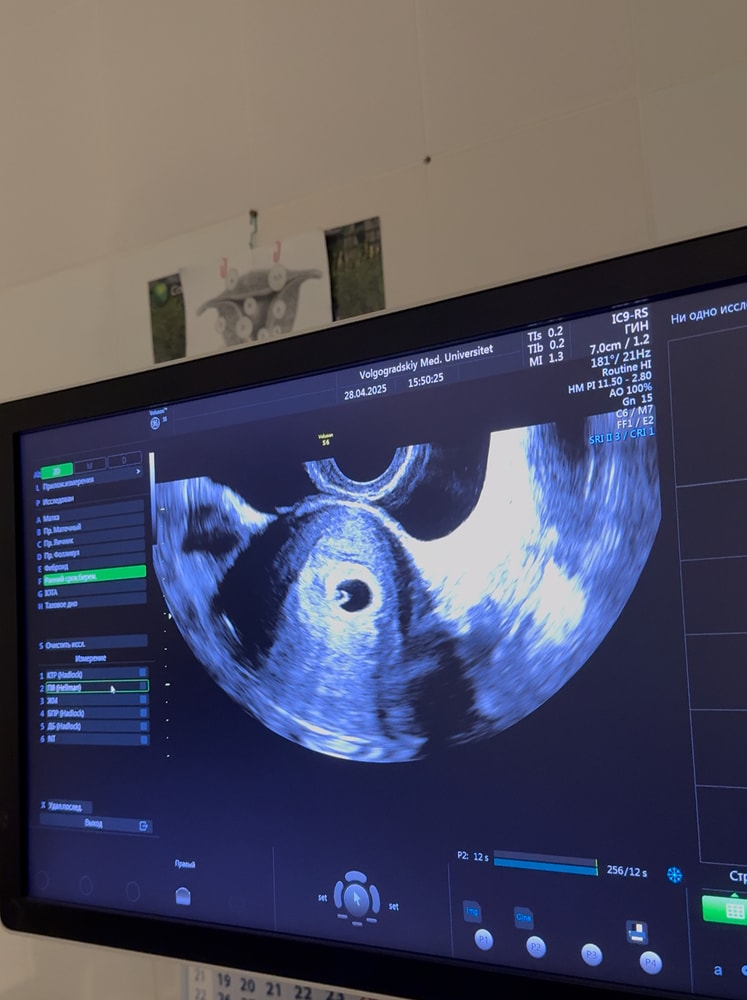

Всё о нашей беременностиНа первом узи на 21дпп, написано пя и жм.

Пересматривая видео с узи, где ре говорит про вот он ваш маленький бриллиантик, я так понимаю что был уже малюсенький эмбриончик, верно же я не ошибаюсь?фото прикрепляю.

Очень переживаю, пока жду следующее узи🤍